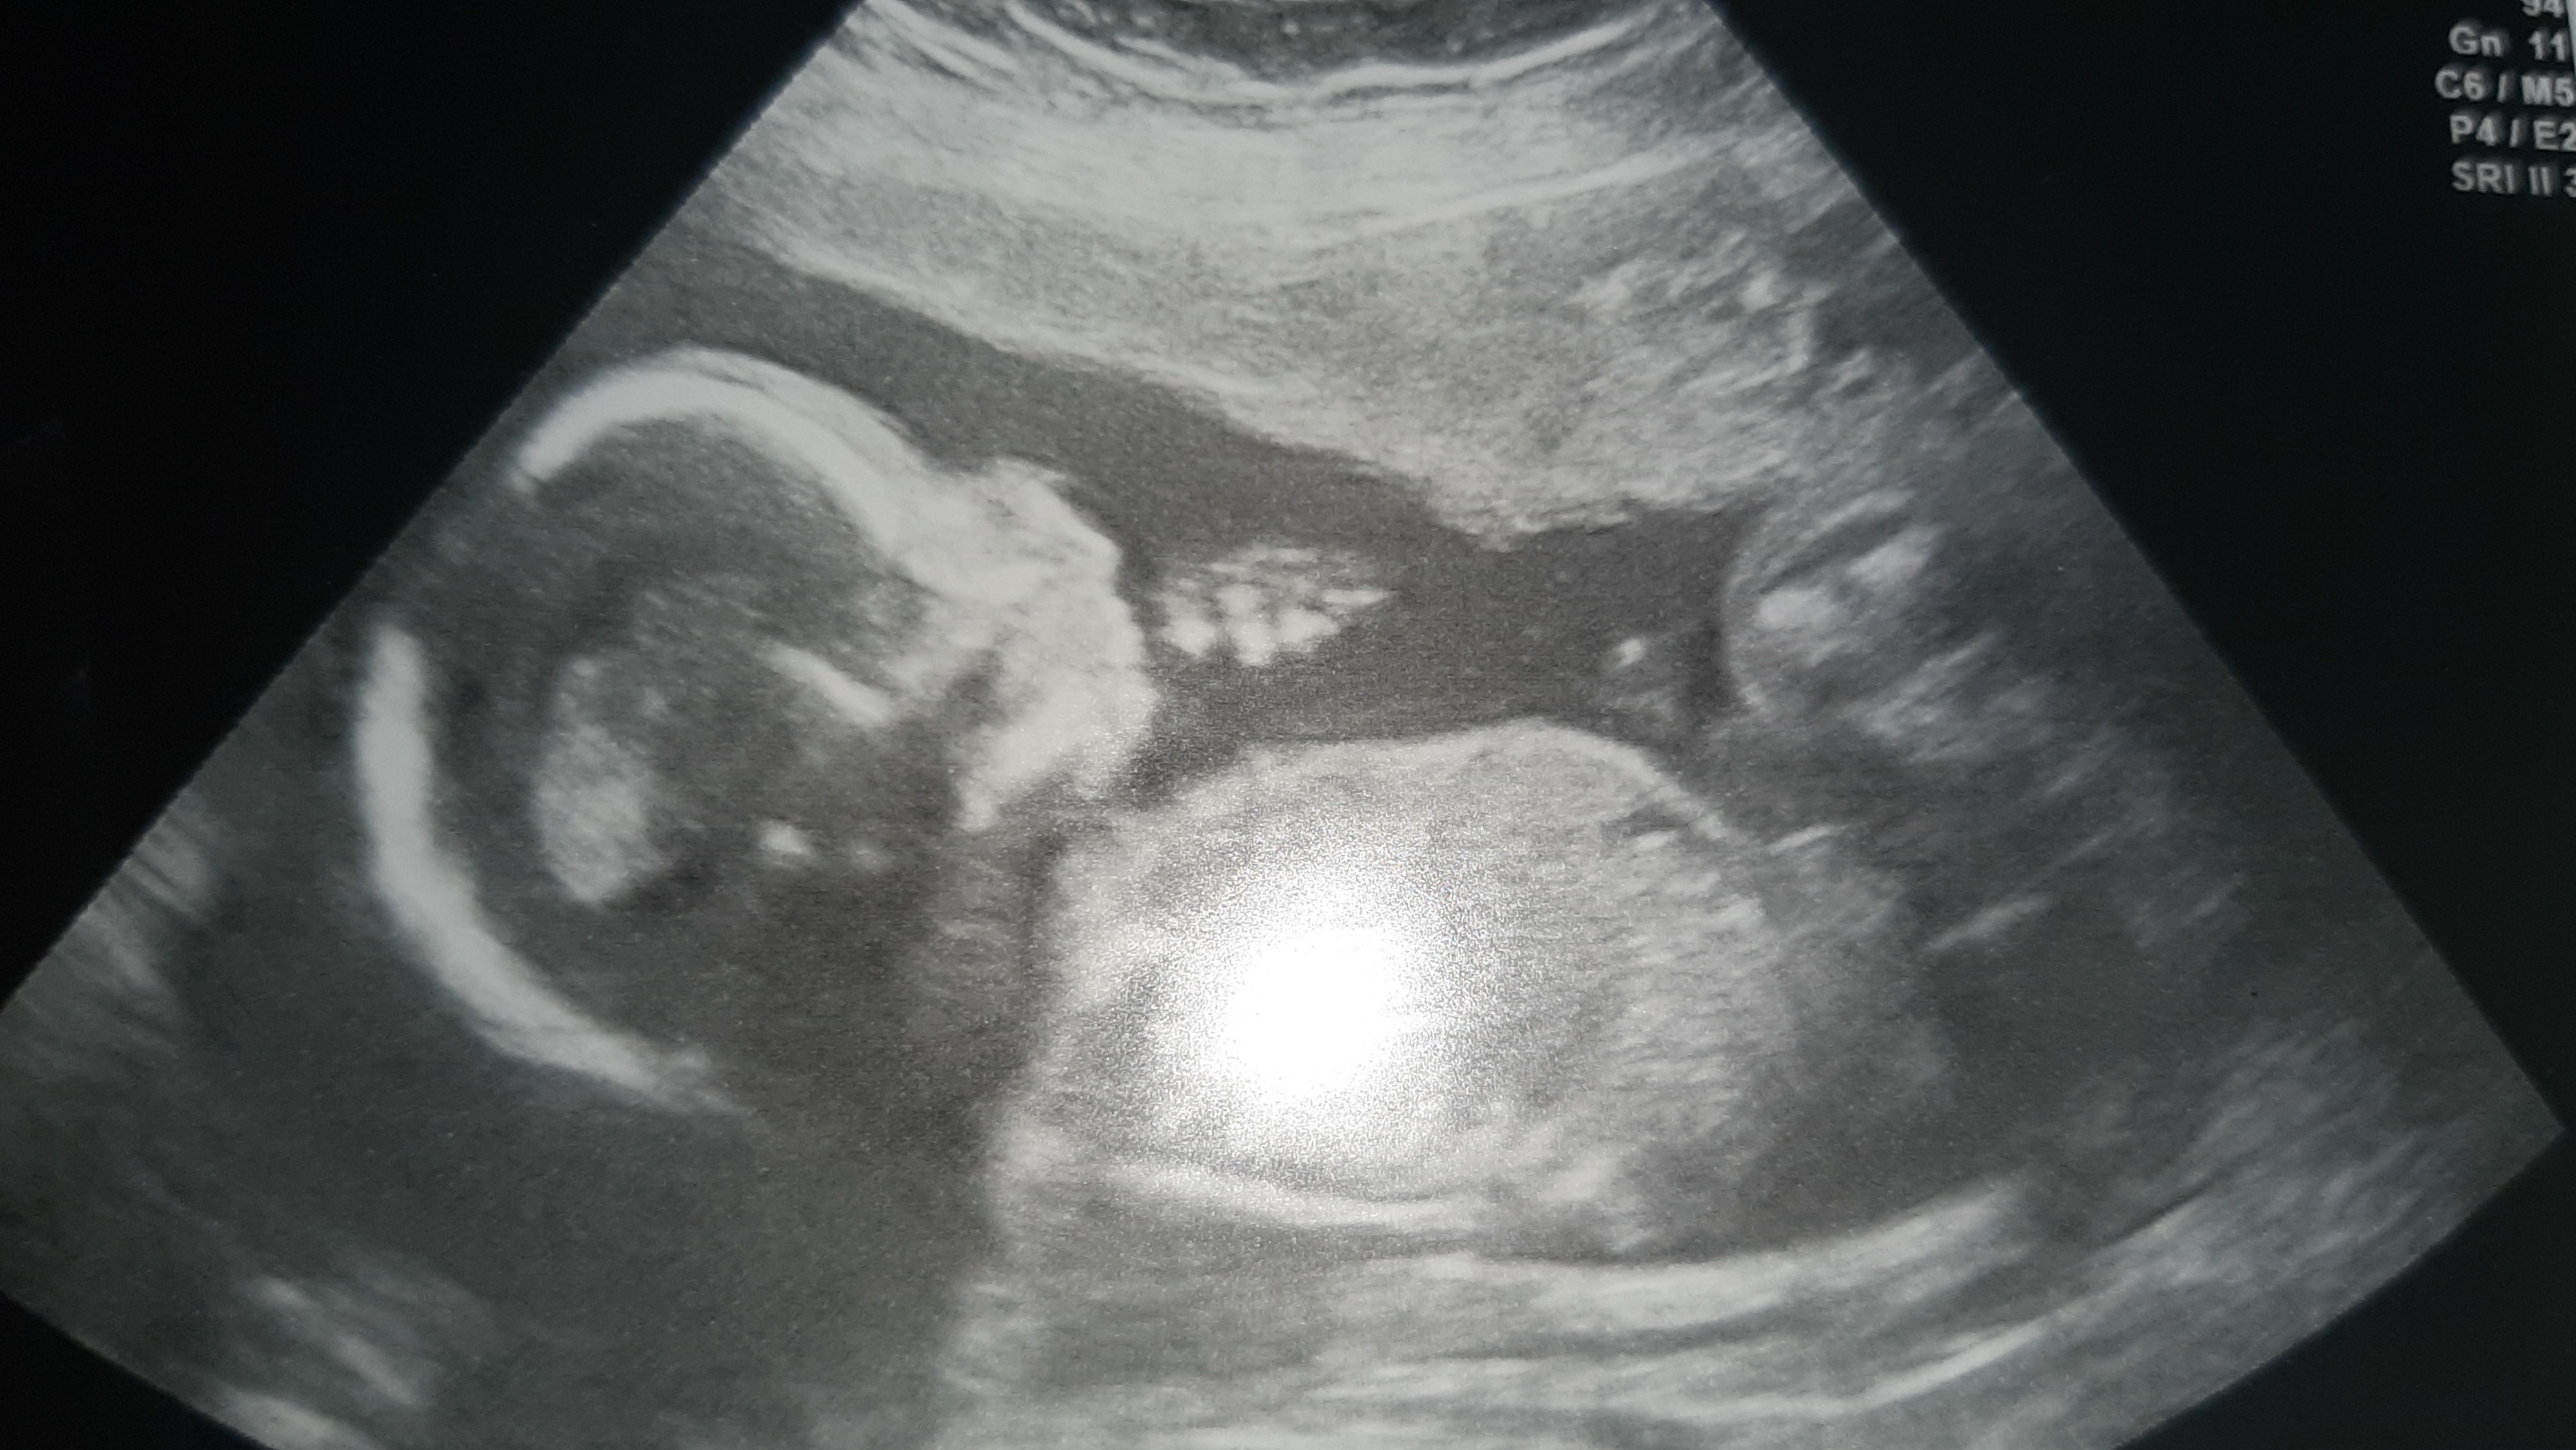

Już nie mogę sie doczekać, żeby ja poznać. Za każdym razem towarzyszą temu cudowi niesamowite emocje ... chociaz pierwsze miesiące zawsze sa tragiczne, aczkolwiek przy tej ciąży poszczescilo mi sie bo nie konalam z powodu mdłości i zapachu masłaNo jak pięknie się uśmiecha z rączka przy ustach.Rośnijcie Zdrowo ,imie które kiedyś mi się podobało i w sumie nadal podoba , ale tym imieniem ochrzciłam swoją chrześnice